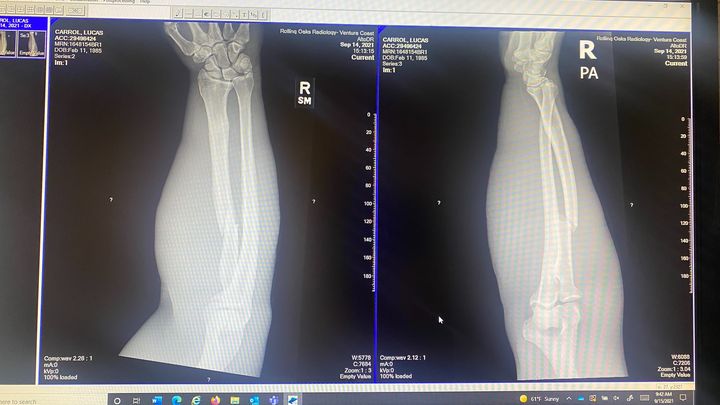

On September 11, 2021 Luke was riding on the 101 freeway when a car cut him off on his motorcycle. He went down at approximately 65 mph, sliding 300 feet on his arms and back. Although we are grateful that his safety gear saved his life, he is suffering from severe road rash on most of his body and from a broken radius in his right arm. We have seen one orthopedic surgeon, and he referred us to a second that will be doing Luke’s surgery. Luke is without medical insurance, and the surgeon requires payment upfront. We are asking for your help with any donations, big or small to go towards his surgery and recovery.